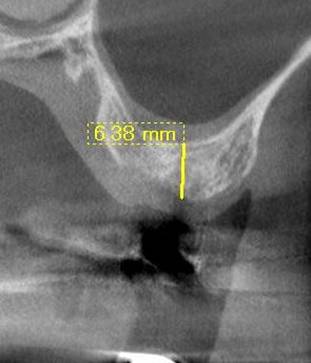

術後のCBCT

インプラントの重大な事故は下顎管から十分な距離をとれば防げます

抜歯部位にインプラントを追加しました。CBCT